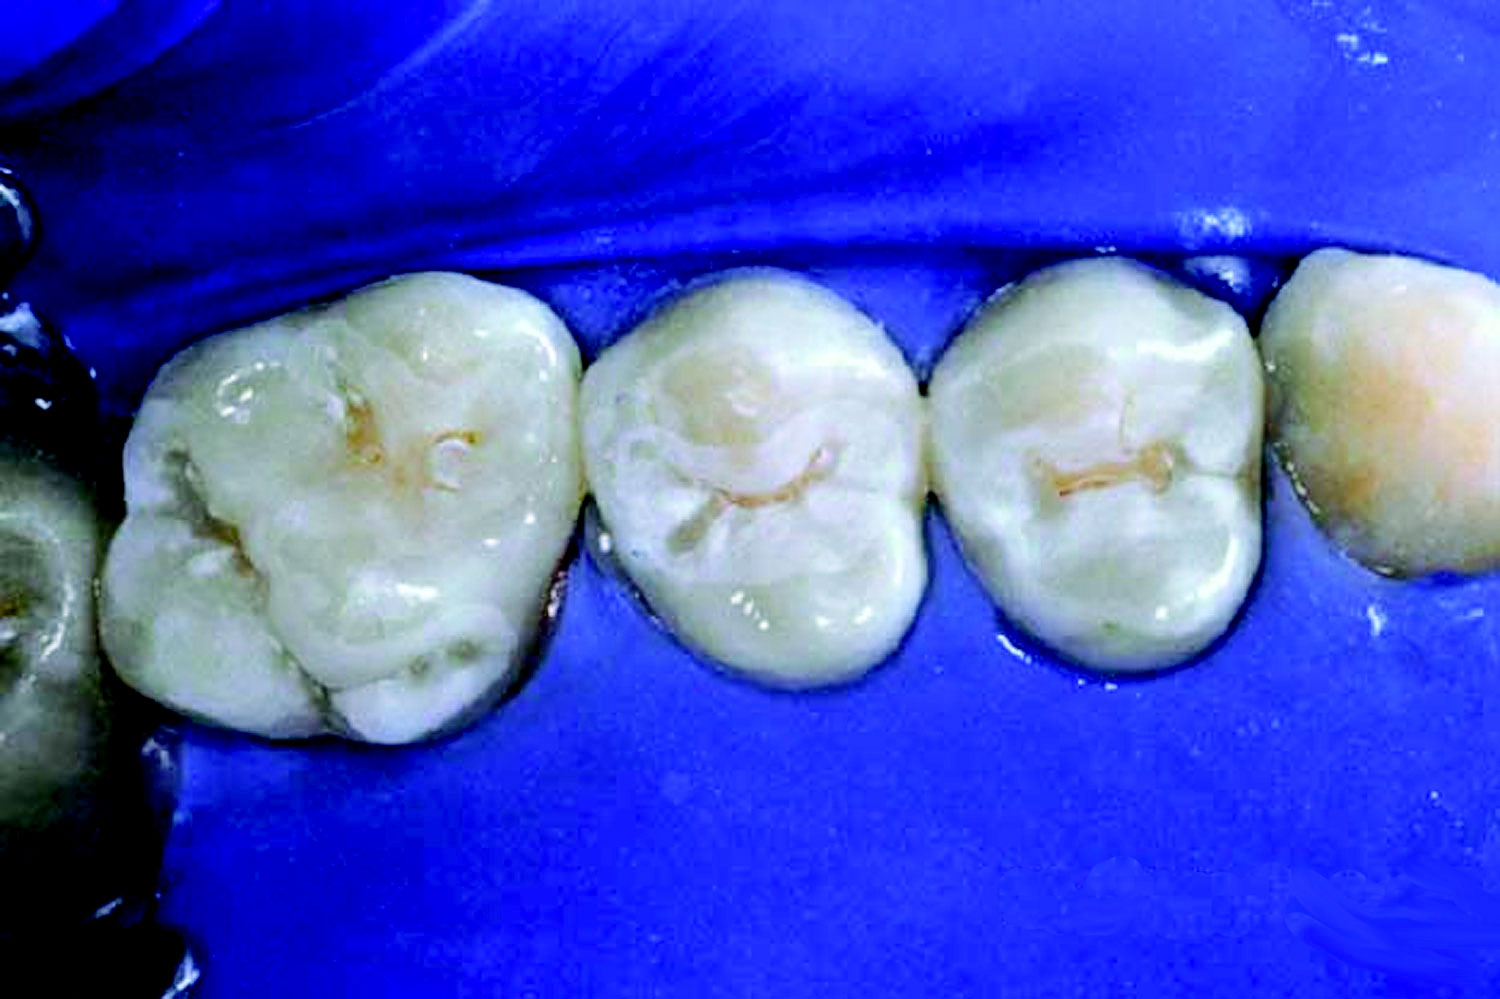

Pit and Fissure Caries (Figure 2). Includes Class I occlusal surfaces of posterior teeth, lingual pits of maxillary incisors, buccal surfaces of mandibular molars.

Sealants have been endorsed by the American Dental Association (ADA) and the United States Public Health Service as being effective in preventing pit and fissure caries. Pit and fissure caries accounts for over 80% of active caries in children; however, these surfaces make up only 15% of the total tooth surfaces. Sealants must not be overlooked as another form of preventive dentist­ry, along with plaque control, fluoride therapy and sugar discipline.

Criteria for Selecting Teeth for Sealants

The criteria for selecting teeth for sealant placement are a deep occlusal fissure, fossa (Figure 19), or incisal lingual pit. A sealant may be contraindicated if: a patient’s behavior does not permit the required dry-field to place sealants; an open carious lesion exists; caries exist on other surfaces of the same tooth and restoration will disrupt an intact sealant; a large occlusal restoration is already present.

Figure 2. Pit and fissure caries.

Figure 2

Figure 19. Deep occlusal fissures.

Figure 19